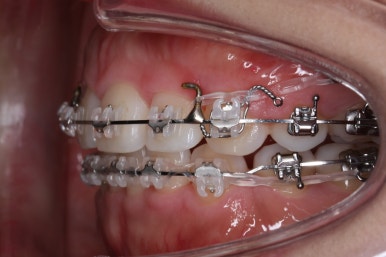

점점 개선이 되고 있는 모습이 보입니다.

정면으로 맞물렸던 교합도 좋아지고 있으며 이로 인해 자연스레 위아래의 앞뒤 간격도 맞닿게 되고 좁아지고 있습니다.

좌측에서 본 모습도 마찬가지입니다.

발치 후에 남아있던 미세한 공간도 없어졌고 윗니도 후방 이동 되면서 교합이 좋아지고 있습니다.

윗니를 봐도 미세하게 남았던 발치를 했던 공간이 없어졌습니다.

마무리 후에 다시 벌어질 수 있는 틈을 유지장치를 붙여 놓았습니다.

앞니, 어금니 맞물림이 좋아진 것을 볼 수 있습니다.

안으로 굽었던 옥니의 각도가 역교정으로 다시 회복이 되었습니다.